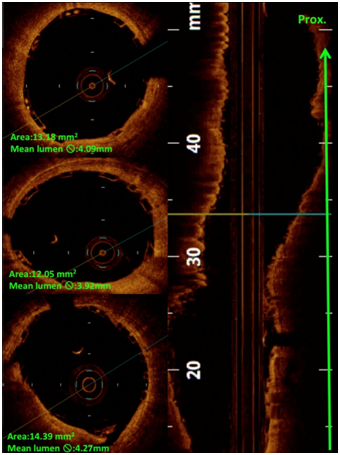

Coronary angiography revealed long, calcified > 40mm length lesion in right coronary artery proximal and middle part (Figure 1). Our decision was to treat this coronary lesion with BRS (Absorb BRS; Abbott Vascular, Santa Clara, CA, USA), following our centre plaque modification strategy, which is plaque modification before scaffold implantation using cutting or scoring balloon. In this case we used cutting balloon pre-dilatation 3.5x15mm 13 bars for each segment three times. Vessel dimensions were pre-analyzed with imaging methods to choose appropriate pre-dilatation balloon size. “PSP (Predilatation, Sizing, Post-dilatation) technique” that improves Absorb implantation is now widely described. Our centre following updated technique which is “IPSP (Imaging, Predilatation, Sizing, Postdilatation” technique. After plaque modification three BRS were implanted with total length 68mm. All scaffolds were implanted with small overlap to avoid uncovered gap which can provoke flow disturbances and possible future problems. Scaffold diameter was 3.5mm. An optimal scaffold apposition to vessel wall was achieved with non-compliant balloon 4.0x20mm. Post-dilatation was done with 15 bars in each segment. Mandatory for this intervention are imaging methods – intravascular ultrasound (IVUS) and optical coherence tomography (OCT). IVUS was performed before PCI, after plaque modification and after BRS implantation (Figure 2). OCT was performed after BRS implantation (Figure 3). Final angiography showed good result of procedure (Figure 4). Patient discharged next day on dual anti-platelet therapy for two years. Now patient reached six-month clinical follow-up with no cardiovascular events or bleeding.

Figure 3 OCT image after scaffold implantation. Image shows good apposition of scaffolds and lumen diameters.